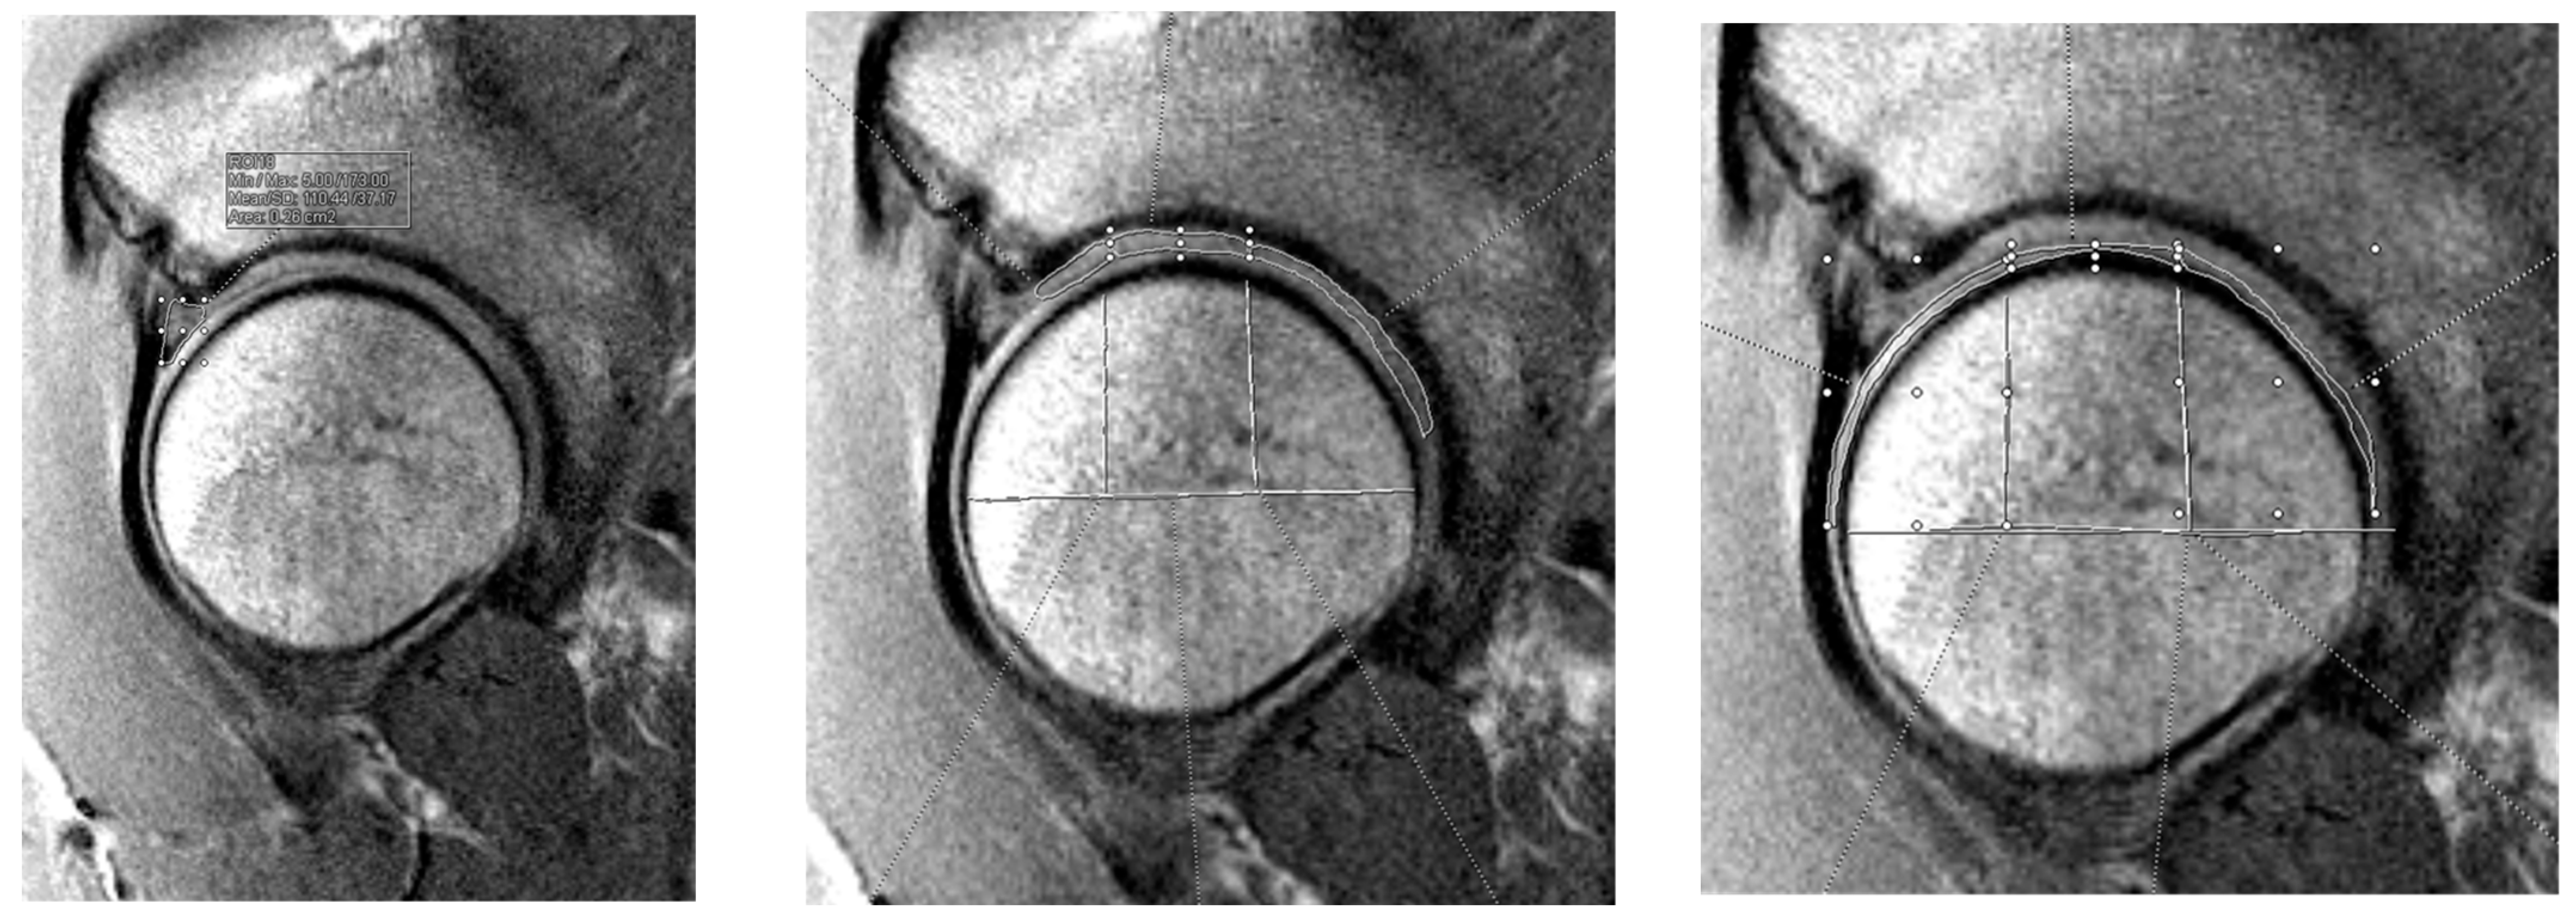

2.2. Preoperative Imaging Technique

- Surowiec, R.K.; Lucas, E.P.; Wilson, K.J.; Saroki, A.J.; Ho, C.P. Clinically Relevant Subregions of Articular Cartilage of the Hip for Analysis and Reporting Quantitative Magnetic Resonance Imaging: A Technical Note. Cartilage 2014, 5, 11–15. [Google Scholar] [CrossRef] [PubMed]